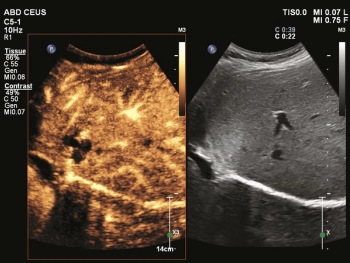

The Microvascular Imaging Super Resolution Contrast-Enhanced Ultrasound application reportedly leverages micro-bubble contrast media to provide enhanced spatial resolution for imaging of malignant lesions.